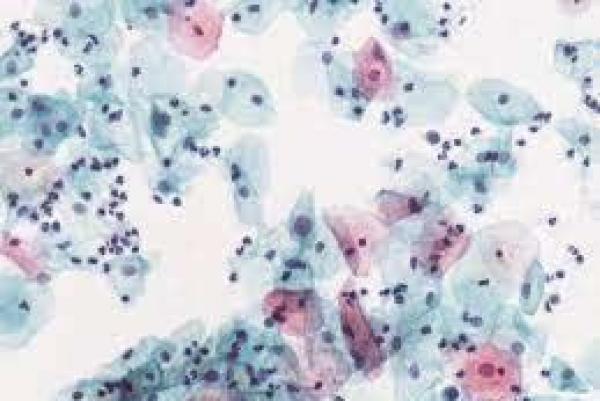

El propósito de este programa es definir el concepto de citología a lo largo de los años y reconocer la importancia de este método diagnóstico actualmente, el participante podrá analizar y valorar las funciones correspondientes a los técnicos de anatomía patológica y citología ante cada prueba diagnóstica; conocerá a fondo la anatomía, histología y citología normal del aparato genital femenino y comprenderá la estructura principal de la célula.

UD1. Citología general. Citología básica y aspectos generales de citodiagnóstico.

2.11. Control de calidad en citología.UD3. Citología del aparato genital femenino.

3.5. Citología de las alteraciones hormonales.UD4. Citología Cervicovaginal.